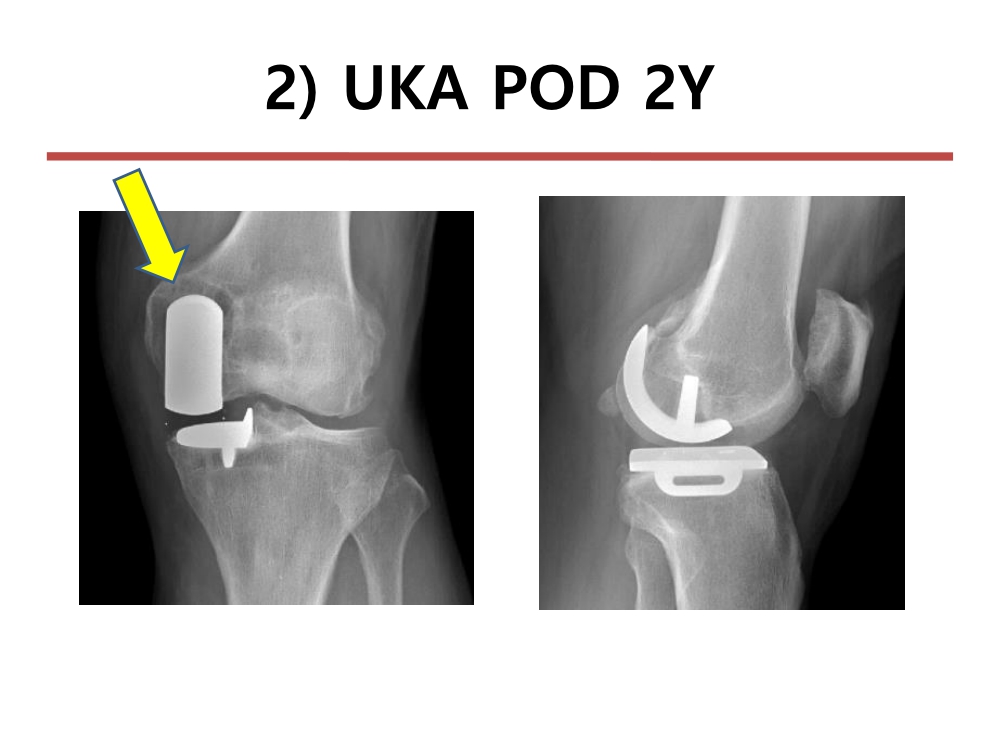

부천대성병원 윤정로 병원장님 슬관절 연수 강좌입니다.